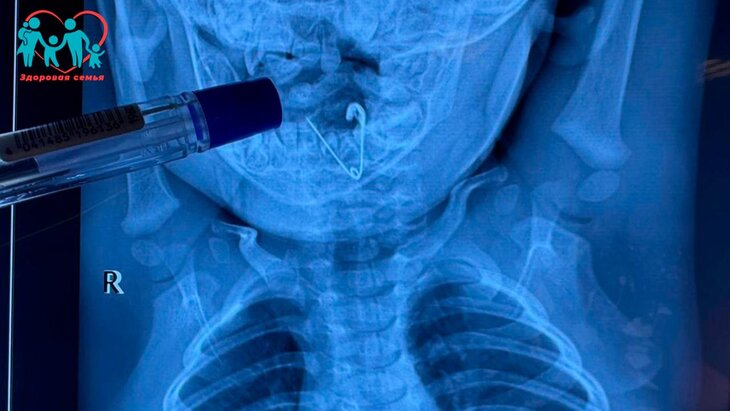

Врачи Краевой детской клинической больницы № 1 Владивостока спасли 7-месячного ребенка, проглотившего прикрепленную к его одеялу раскрытую булавку-оберег. Об этом сообщает пресс-служба медучреждения.

После этого родители незамедлительно вызвали скорую помощь. Прибывшая бригада медиков доставила младенца в центральную районную больницу Черниговки, где ему сделали рентгенографию грудной клетки. Исследование подтвердило наличие инородного тела в пищеводе.

После этого было принято решение о переводе мальчика в Краевую детскую клиническую больницу № 1. Там врачи, проведя повторный рентген, успешно извлекли предмет из него с помощью щипцов и эндоскопической техники.